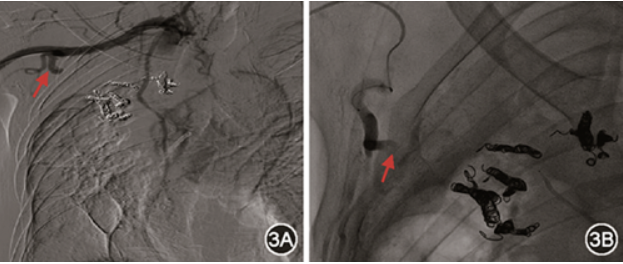

辅助检查:红细胞沉降率64 mm/1 h,白蛋白29.6 g/L,血曲霉半乳甘露聚糖(GM)试验结果升高:0.54 μg/L,血真菌(1-3)-β-D葡聚糖(G)试验<31.25 ng/L。心脏彩色多普勒超声提示:心脏结构未见异常;心脏左心室收缩功能正常。肺泡灌洗液GM试验结果为0.85 μg/L。肺泡灌洗液tNGS:烟曲霉(序列数62)、屎肠球菌(序列数54)、巨细胞病毒(序列数205)。支气管动脉、肺动静脉CT血管成像显示:右肺上叶毁损,右肺上叶可见空洞,左肺肺气肿、肺大泡(肺窗,图1A);支气管动脉迂曲增粗,肺动脉瘤样扩张,肺静脉未见异常(纵隔窗,图1B)。诊断为慢性肺曲霉病,结核性毁损肺。

图1 患者胸部CT可见右肺上叶空洞(图1A红色箭头),空洞内可见空气新月征,考虑为曲菌球,左肺肺气肿、肺大泡(图1A红圈);CTA提示支气管动脉迂曲增粗(图1B红色箭头)、肺动脉瘤样扩张(图1B红圈)